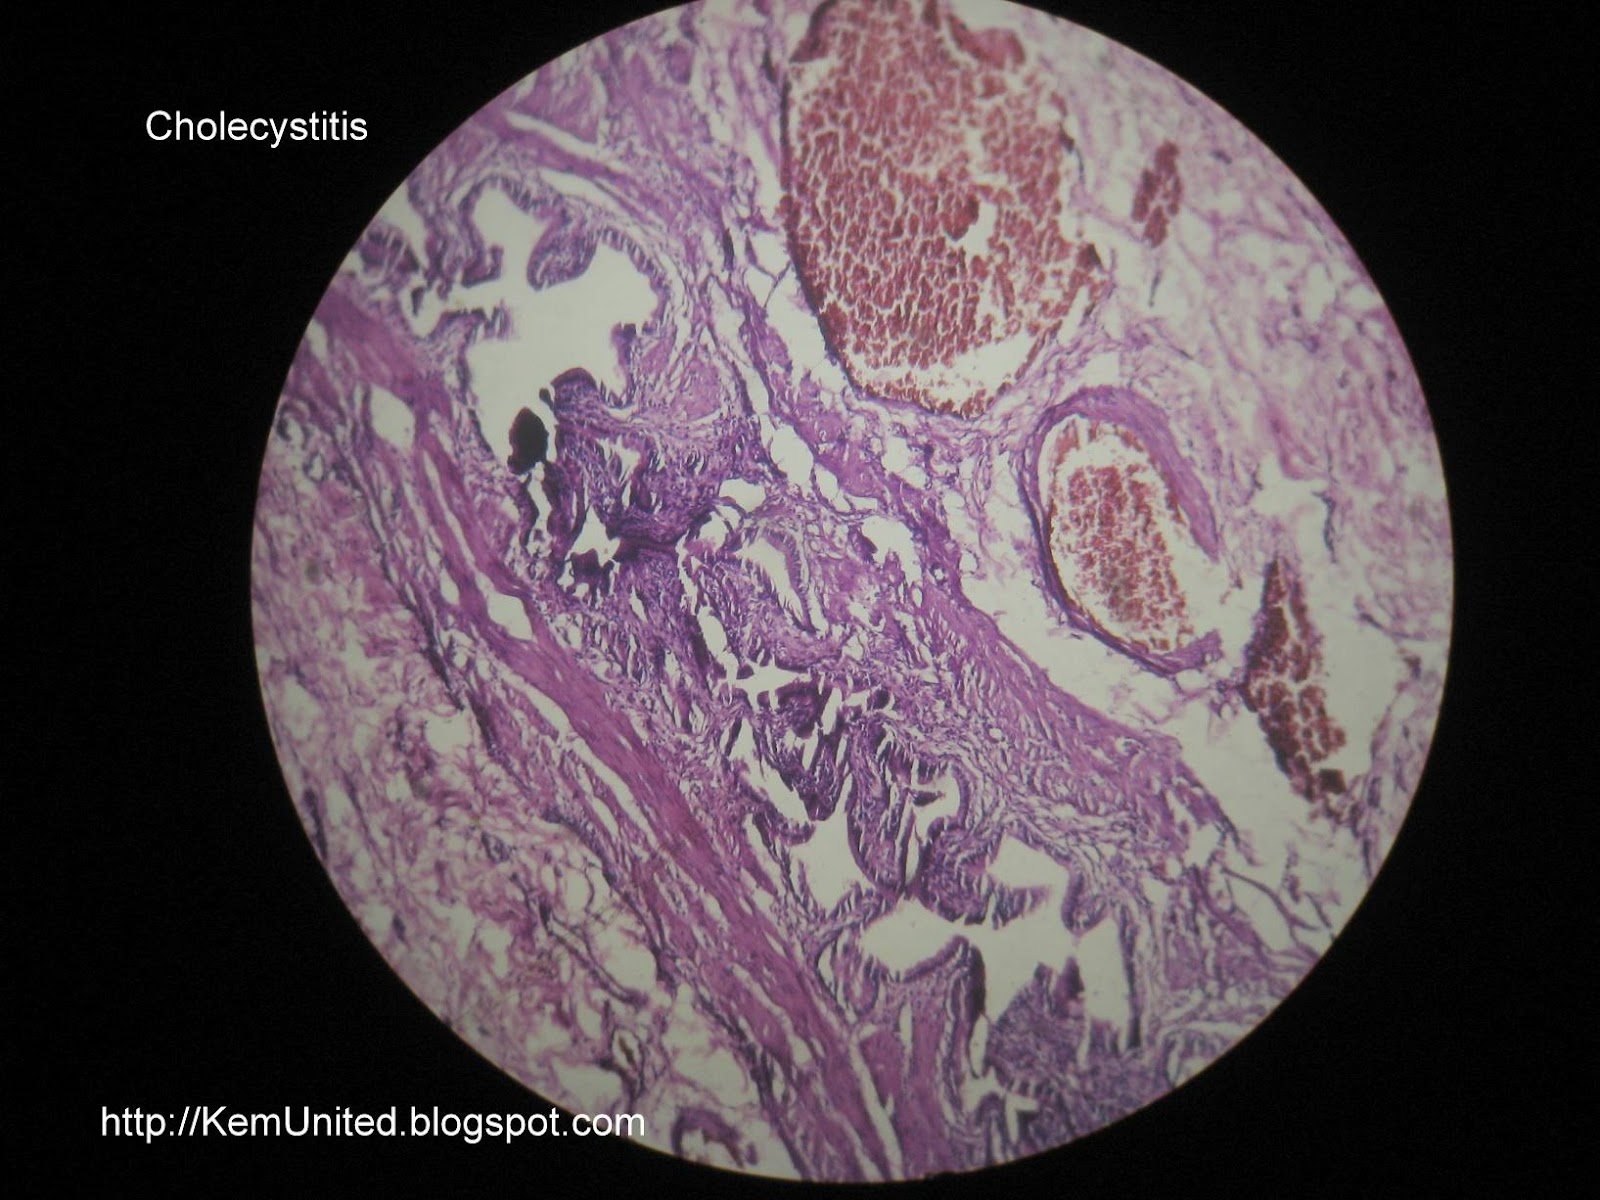

4th Year: Pathology slides

4th year pathology slides Latest shown on 30-12-2011